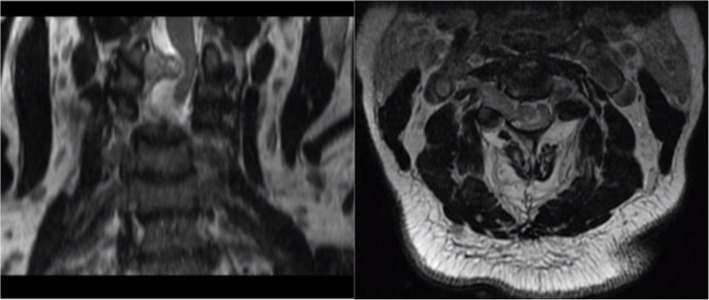

神经鞘瘤是后纵隔最常见的神经源性肿瘤,但在前纵隔很少发现(mediastinum 4,2020;中华放射医学杂志13(4):175-7。我们报告一个大的前纵隔神经鞘瘤引起心脏压迫,同时颈椎病变引起右侧无力。目前文献中只有少数病例报告描述了这种肿瘤的前位,更罕见的是同时有症状性宫颈病变。我们提出这个病例是为了强调这种罕见的发现,并提高对这种潜在诊断的认识。

Schwannoma is the most common neurogenic tumor in the posterior mediastinum, however it is rarely found in the anterior mediastinum (Mediastinum 4, 2020; Radiat Med 13(4):175-7). We report a large anterior mediastinal schwannoma causing cardiac compression along with a concurrent cervical spine lesion causing right-sided weakness. Current literature having only a few case reports describing an anterior location for this neoplasm and even rarer to have a concurrent symptomatic cervical lesion. We present this case to highlight this rare finding and increase awareness of this potential diagnosis.